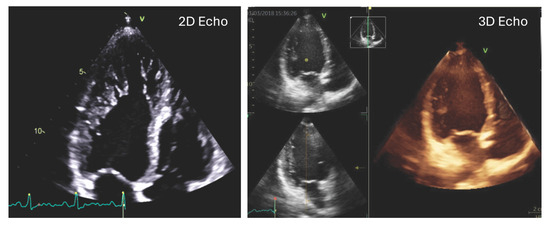

Three-dimensional transthoracic echocardiography (3D TTE) has recently gained attention as a valuable imaging modality that enables comprehensive cardiac assessment by providing spatially detailed views of cardiac structures and motion [9,10]. Although it is less optimal for depicting fine trabecular details, 3D TTE offers high accuracy in quantifying functional and volumetric parameters (Figure 1), as also emphasized in recent guideline recommendations. A novel analytical approach based on 3D TTE facilitates the evaluation of right ventricular (RV) volumes, global function, and directional motion along three orthogonal planes that correspond to the anatomical fiber architecture of the RV [11]. Prior studies across various cardiac conditions have indicated that alterations in RV motion patterns may hold prognostic relevance. Nevertheless, the specific features of RV mechanics, including directional contraction behavior, have not yet been systematically characterized in individuals with LVNC morphology.

Figure 1. Representative 2D and 3D transthoracic echocardiographic images of a patient with left ventricular hypertrabeculation.